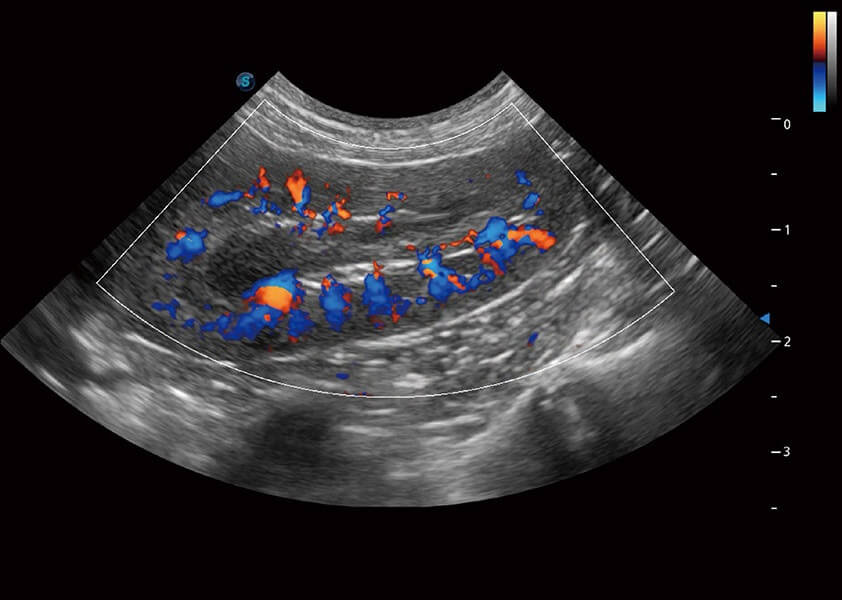

(犬)肾脏血流

SR Flow 高分辨率血流成像

能够清晰显示细小、低速血流图像,获取传统彩色多普勒技术难以得到的细节和信息。

Micro F 显微血流成像

通过创新的Matrix E自适应滤波器和超长时间域算法,极大提升超低速微细血流的检出能力,同时更精准地滤除软组织和噪声信号,为兽用医生提供以往无法通过常规血流获得的疾病诊断信息。